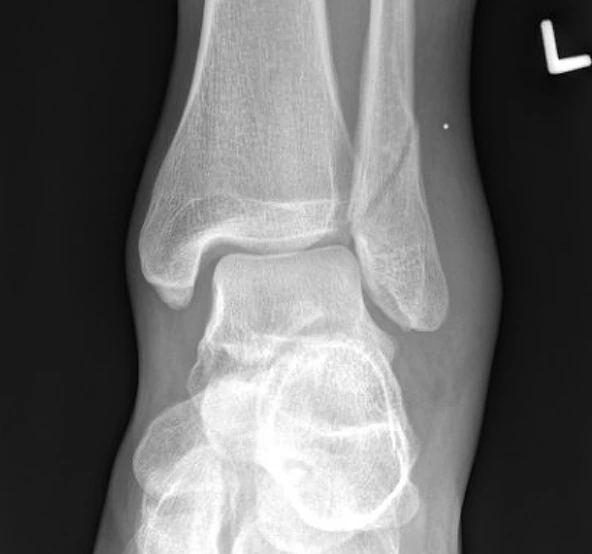

Ankle Fractures

Ankle fractures are often the result of twisting injuries or high-impact trauma. They can involve the tibia, fibula, or both, and may require surgical intervention for proper alignment and healing.